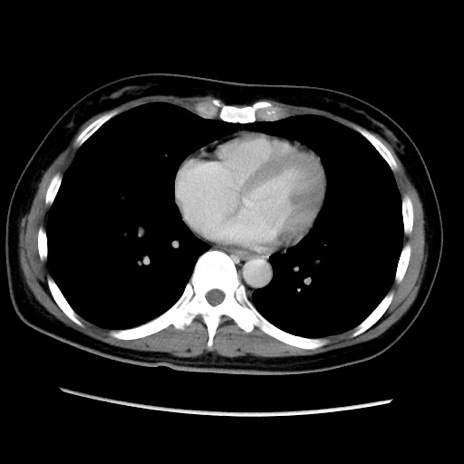

MRI(4日後)